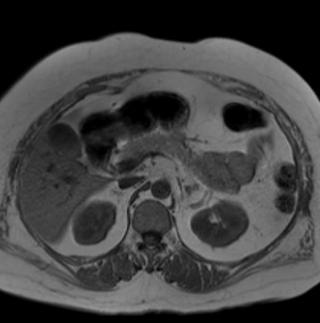

(Слева) КТ с контрастированием, аксиальная проекция: крупное яйцевидное образование левой почки с гетерогенным контрастированием. Спереди расположен небольшой объем неизмененной почечной паренхимы. Сосуды левой почки смещены, но не вовлечены в процесс, лимфаденопатия отсутствует. При исследовании резецированного биоп-тата установлена гемангиоперицитома.

(Справа) МРТ, Т1-ВИ, аксиальная проекция: крупное образование, смещающее большую часть правой почки. Образование имеет гомогенный сигнал низкой интенсивности, смещает почечные сосуды, но не прорастает их.